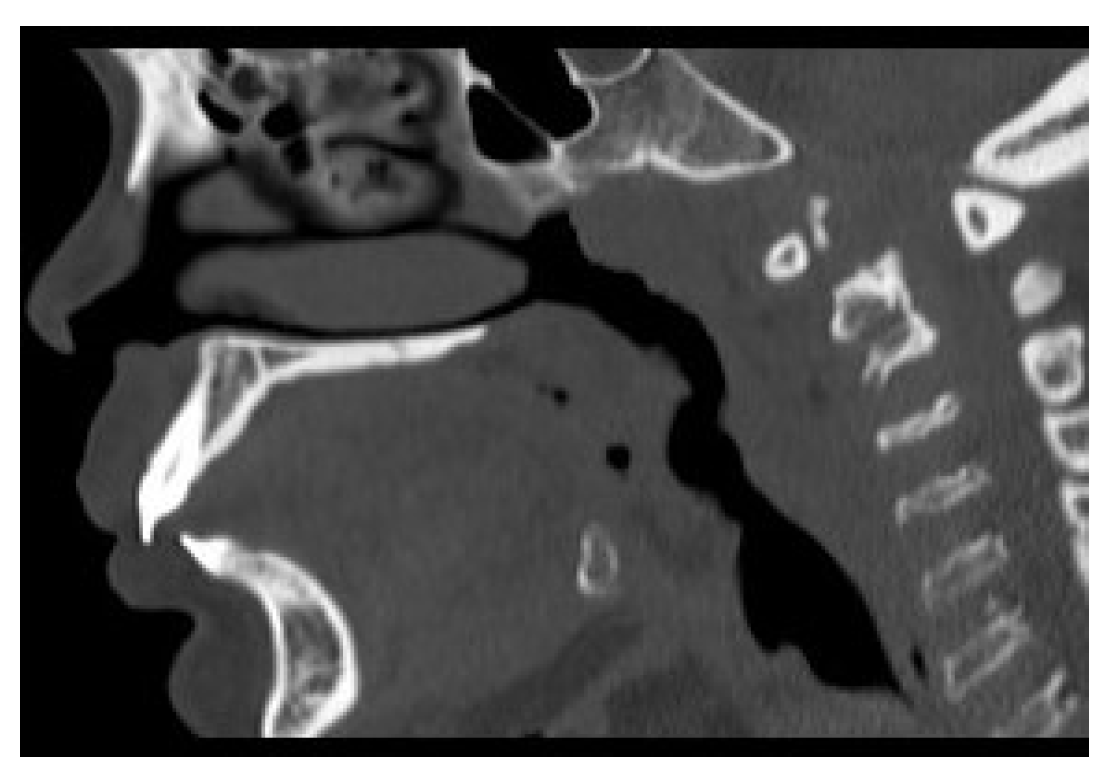

3.2. Cross-Sectional Imaging

3.3. 3-Dimensional Reconstruction (3D) and Virtual Endoscopy (VE)